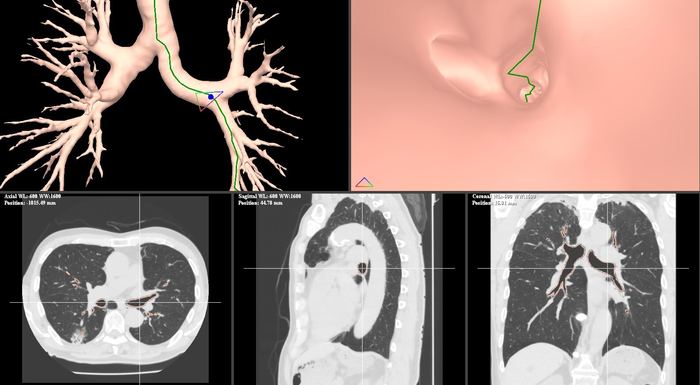

Growth RTV 放射線治療計画UI Growth RTV VBN気管支ナビゲーション Growth RTV AI臓器自動抽出 Growth RTV D-MARアーチファクト低減

放射線治療、呼吸器外科、整形外科向けOEM製品等

Growth RTVエンジンを活用したOEM製品として、放射線治療・呼吸器外科・整形外科等の領域で組み込み提供。

• 放射線治療計画システム向け組み込み

• 呼吸器外科・整形外科対応AI機能